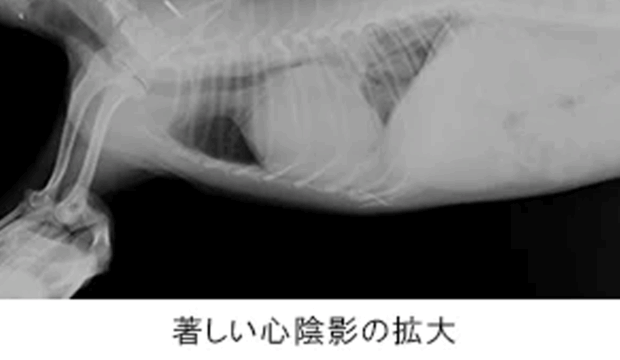

猫 MIX 18歳

呼吸が速い

呼吸促迫、食欲低下

胸部レントゲンにより、肺野のびまん性不透過性亢進像・左側前葉部の無気肺が確認され、当初肺炎が疑われていましたが心臓超音波検査により拘束型心筋症と診断。

| 猫で2番目に多い心筋症の一つです。強心剤の内服・利尿剤に良好に反応し呼吸状態は改善、元気・食欲ともに回復し良好な一般状態を維持しています。 拘束型心筋症は大動脈血栓塞栓症を併発することがあるため、抗血栓薬を用い血栓の予防を合わせて実施することが大切です。 |